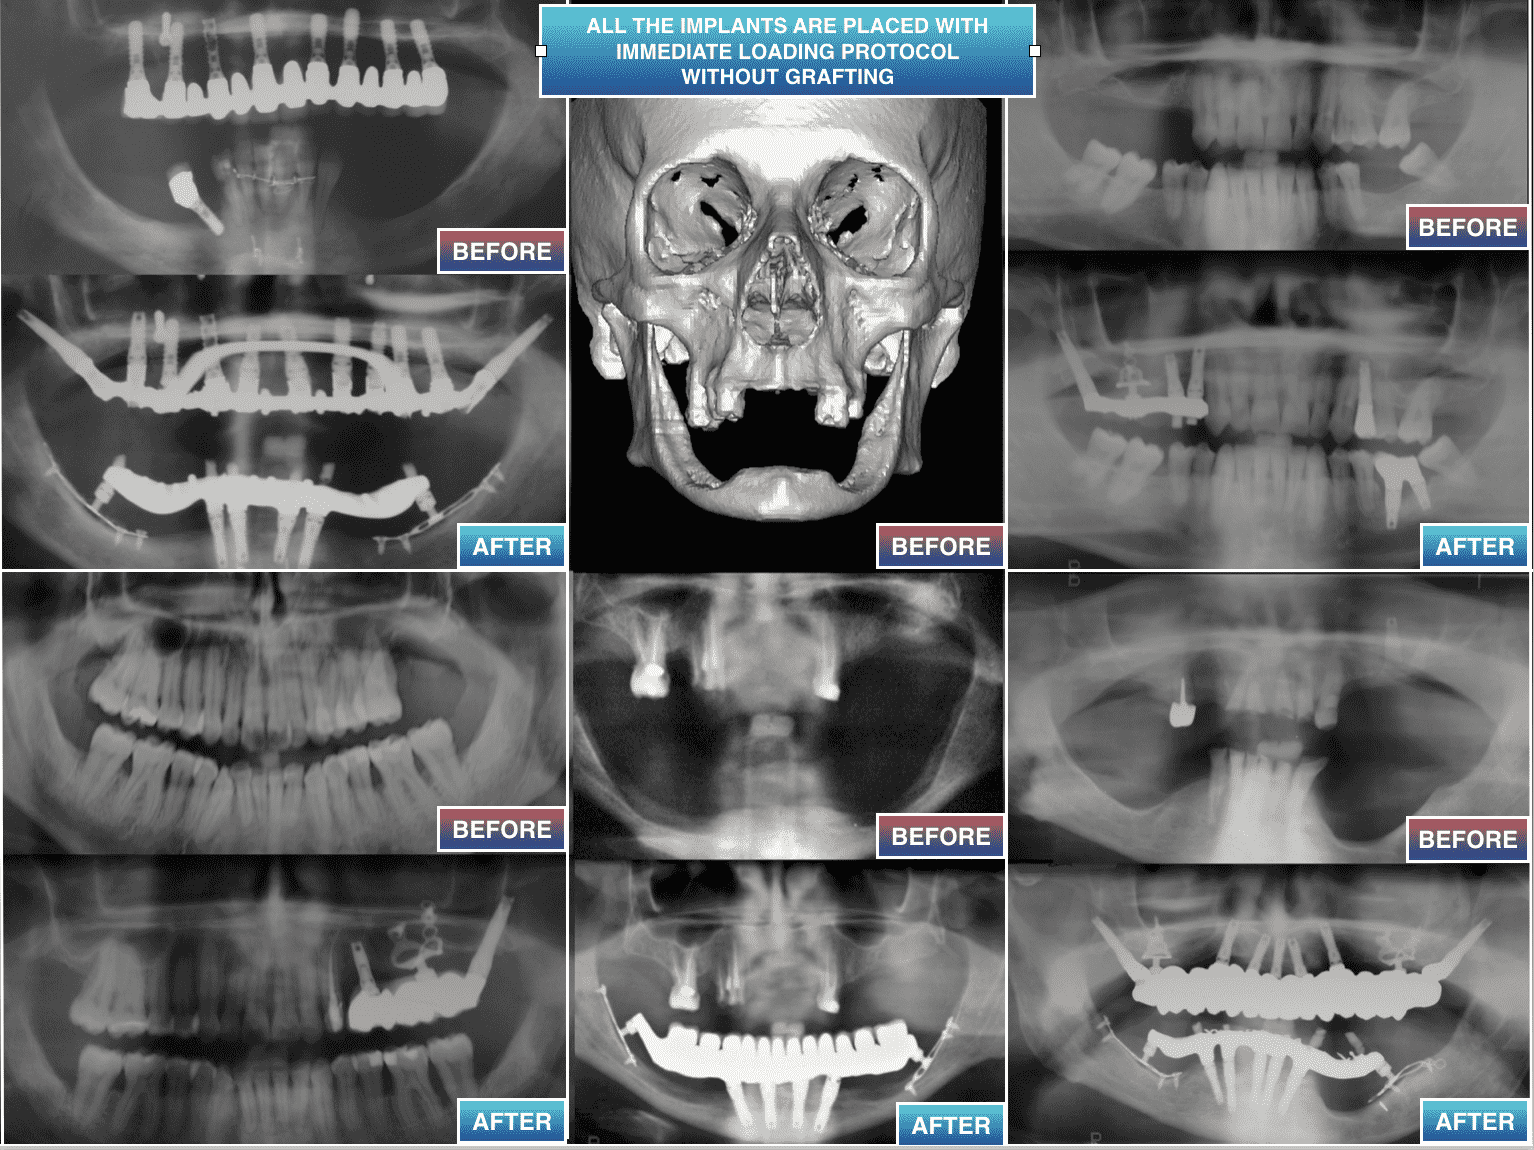

COMMENT NE PAS PERDRE DE PATIENTS

QUAND VOUS NE POUVEZ PAS GREFFER ?

Depuis plus de 30 ans nous pratiquons des chirurgies

en implantologie dentaire, enseignées en Universités,

sans passer systématiquement par les greffes,

quand elles ne peuvent être appliquées, ou quand elles ont échoué

- 2)  COMMENT POSER DES  IMPLANTS SANS GREFFER

QUAND LA HAUTEUR OSSEUSE DISPONIBLE EST DE MOINS DE 4 MM